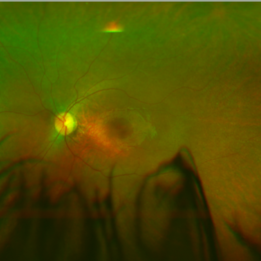

Right and left eye of a patient with LCA RPE65 showing vascular attenuation and RPE changes.

Condition/keywords: Leber's congenital amaurosis, retinal pigment epithelium, retinal pigment epithelium (RPE) changes, vascular attenuation